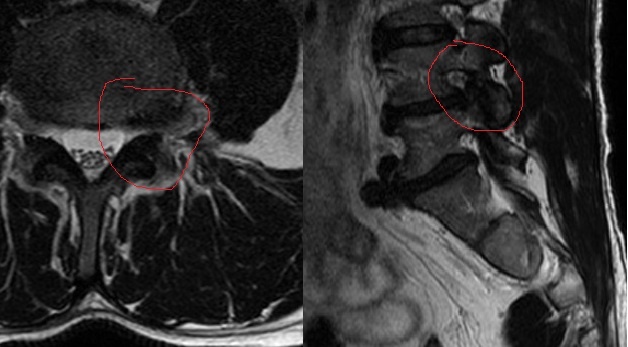

Масштабная экструзия диска L4-5 в область левого фораминарного отверстия с краниальной миграцией секвестра. Снимок сделан в пределах месяца после появления болевых ощущений и легкого неврологического дефицита.

По данному случаю стоит отметить неполную резорбцию, что вполне можно связать с курсом блокад, проведенных в начале терапии (вообще, подход к терапии – отдельная история, требующая отдельной же заметки).